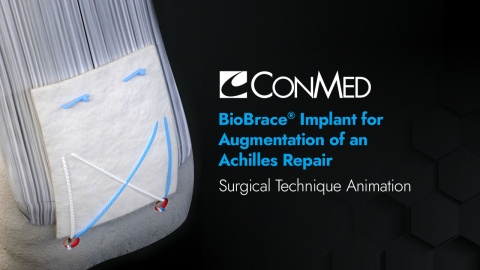

BioBrace® Implant for Augmentation of an Achilles Repair